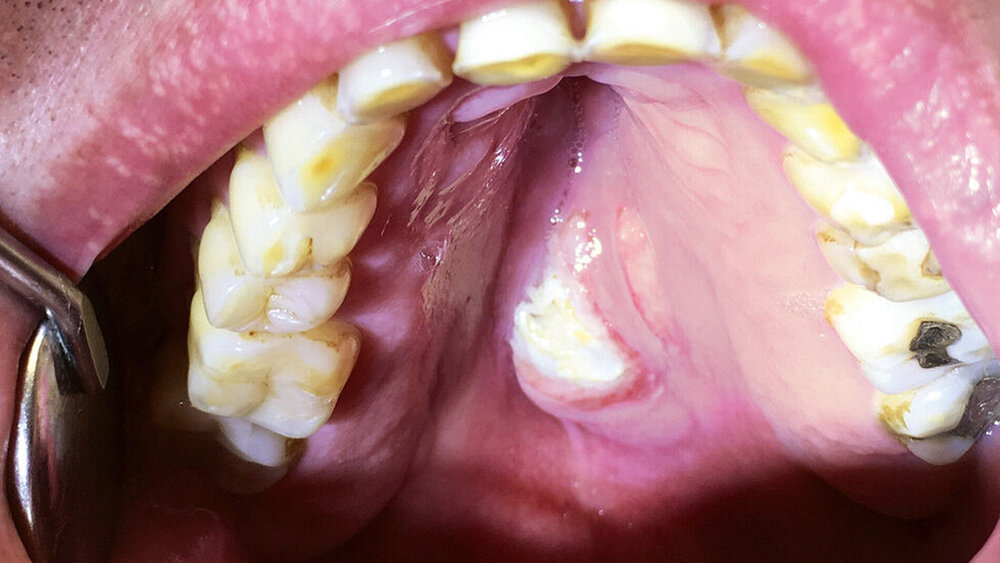

Bei der extraoralen Inspektion ergaben sich keine Besonderheiten. Intraoral zeigte sich eine etwa 3 cm große, erhabene, unverschiebliche, schmerzfreie Schwellung in der Gaumenmitte, am Übergang vom harten zum weichen Gaumen. Diese war vom Tastbefund prall elastisch, die Oberfläche ulzeriert und fibrinbelegt. Die Ränder des Befunds waren gerötet. Die Palpation der Halsregion ergab keine Auffälligkeit.